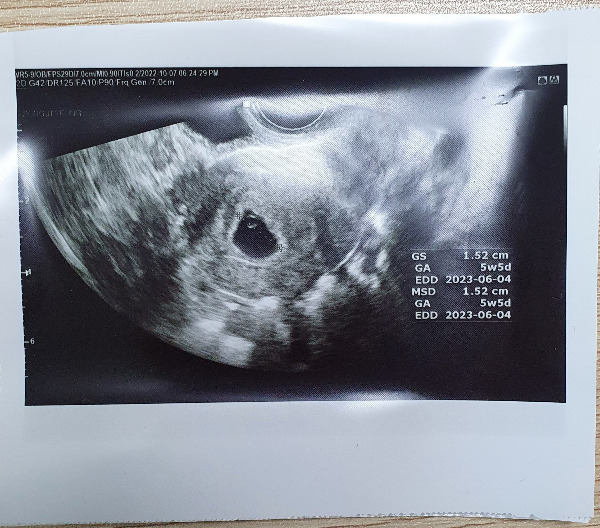

KakaoTalk_20221012_165006992_03.jpg 까꿍이 첫 초음파 사진

임신 5주차였고 초음파상으로 난황과 아기집이 보이는 상태였다. 아기집 위치도 좋다고 했고 자궁도 깨끗하다고 했다. 너무 다행이었다. 이때만 해도 극초기여서 앞으로의 일이 어떻게 될지 모든 게 다 미지의 세계였지만 내 인생에 나와 사랑하는 사람을 닮은 아기가 생겼다니 생각지 못했던 축복 같은 일이 내게도 일어나서 그저 신기하고 감사했다.